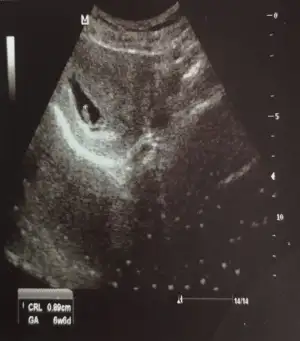

Kız buna göre tabi en iyi 11 12 13 haftalar olmalıIkra meyra canım merhaba 6+6daki karından usgmiz bakabilir misin? Allah herkese sağlıklı akıllı bebisler nasip etsin elbet isteğimiz bu ama insan merak ediyor yani

![]()

Kız gibi sanki. Başka USG varsa paylaşın emin olamadım

Kız gibi sanki. Başka USG varsa paylaşın emin olamadım![]()